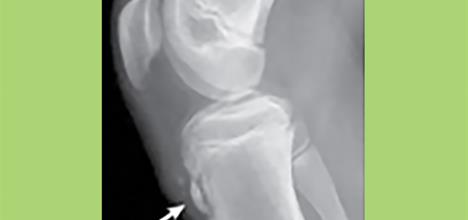

Children have growth plates called apophyses where muscles and tendons attach. The patellar tendon of the knee connects the knee cap quadriceps (thigh) muscles to the shin bone at the tibial tubercle (bump below the knee). This growth plate is attached to the shin bone by cartilage and is subject to stress from overuse when the quadriceps

muscles repetitively pull while running or jumping.